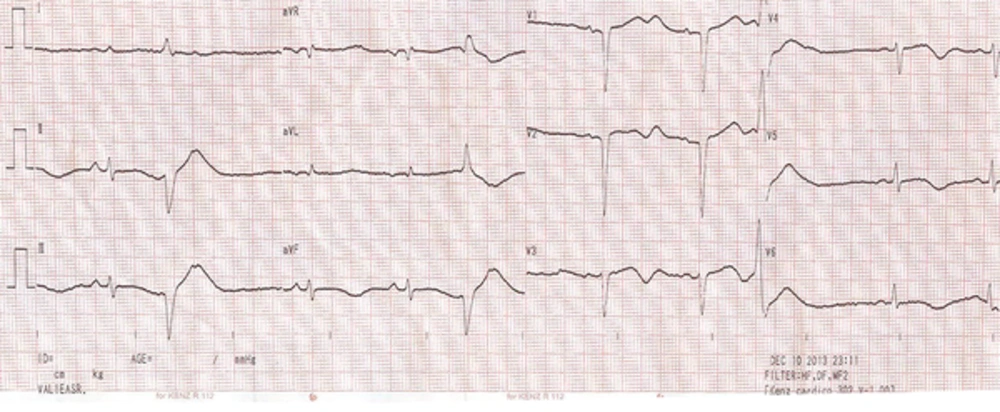

Examination of different systems of the body did not show any abnormalities. The patient was referred for cardiac care to monitor ECG changes, including T-wave inversion in the inferior leads and prolonged QT interval (Figure 1). In the initial evaluation, troponin I (TPI) was negative, renal function and electrolyte level were normal, and no disorder was found on ECG. As ordered by the cardiologist, the patient was hospitalized in the cardiac care unit (CCU) for 24-hour monitoring due to ECG abnormalities. Three hours after admission, the patient showed ventricular tachycardia (VT), along with loss of consciousness. He was treated with synchronized shocks at 200 J and intravenous magnesium sulfate (2 g). Along with magnesium sulfate, lidocaine infusion at a dose of 2 mg/kg/h was initiated because of recurrent and resistant VT (Figure 2).